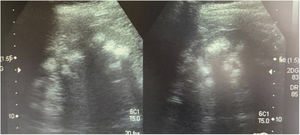

Casos clínicosCaso 1Paciente femenino de 4 años y 3 meses de edad. Peso al nacer 2.800g, talla 48cm y Apgar 8/9. Como antecedente presenta avidez por el agua y la sal. Poliuria y nicturia en la etapa de lactante. Fue hospitalizada en 11 ocasiones por fiebre sin foco aparente. A los 20 meses de edad fue diagnosticada de herpes zóster y tratada con aciclovir durante 7 días; a continuación, presentó un cuadro diarreico, deshidratación moderada y flacidez generalizada con incapacidad para caminar. Fue hospitalizada en el Hospital General de Zona con la sospecha de síndrome de Guillain-Barré; su peso era 9,5kg y la talla 82cm (ambos en percentil 10). Se observó hipopotasemia (2,5mEq/l) y acidosis metabólica. Tras instaurarse tratamiento intravenoso y la corrección del desequilibrio hidroelectrolítico, mejoró la fuerza muscular logrando la deambulación. Sin embargo, persistía la acidosis metabólica hiperclorémica. Los datos bioquímicos y los hallazgos de la ecografía aparecen en la tabla 2 y la figura 2, respectivamente. La valoración audiológica no mostró datos de hipoacusia neurosensorial. El estudio oftalmológico fue normal. Se realizó una prueba de acidificación urinaria con bicarbonato de sodio y acetazolamida según un protocolo descrito previamente (prueba de pCO2 urinaria máxima)11–13. La prueba se realizó sin complicaciones, fue bien tolerada y se consideró valida al conseguirse una bicarbonaturia superior a 80mEq/l. Se cuantificó una pCO2 urinaria máxima de 80mmHg a los 60min (anormal<70mmHg) (tabla 3). Se comprobó que la paciente es portadora de la misma mutación que su madre. Después de 3 años de tratamiento con álcalis ha mejorado el peso y la talla, a saber, 16,5kg (percentil 47) y 103cm (percentil 34), respectivamente. En la actualidad recibe tratamiento con citrato de potasio (4,5mEq/kg/día) con lo que ha remitido la hipercalciuria. La TA es normal (89/59mmHg).

Paciente masculino de 8 años y 11 meses de edad sin antecedentes perinatales de importancia (peso 2,9kg, talla 50cm y Apgar 9/10). Avidez por el agua y la sal desde los 2 años de edad, aproximadamente. Precisó 3 hospitalizaciones durante su primer año de vida por episodios de deshidratación moderada. Acudió hasta en 24 ocasiones al servicio de urgencias de su localidad por la presencia de fiebre. En algunas ocasiones se catalogó de infección de vías respiratorias, si bien, en la mayoría de los casos no se detectó una causa aparente de la misma. Al efectuarse el diagnóstico de ATRd a su hermana, se realizó el abordaje diagnóstico. Su peso era 18kg (percentil 5) y la talla 111cm (percentil 3). Se observó acidosis metabólica hiperclorémica con anión restante normal, hipercalciuria, hipocitraturia severa (tabla 2) y nefrocalcinosis grado III. La valoración audiológica fue normal. La pCO2 urinaria máxima también fue normal (tabla 3). También, después de tres años de tratamiento con álcalis han mejorado tanto el peso (23kg, percentil 8) como la talla (122cm, percentil 17). Recibe tratamiento con citrato de potasio (5mEq/kg/día). El estudio genético mostró la misma mutación que su madre y su hermana.

Ecografía realizada a la madre de los pacientes. Riñones con ecogenicidad heterogénea a expensas de un aumento de la ecogenicidad de las pirámides renales compatible con nefrocalcinosis medular bilateral grado II-III. La relación córtico medular es poco nítida, con datos de nefropatía crónica difusa.